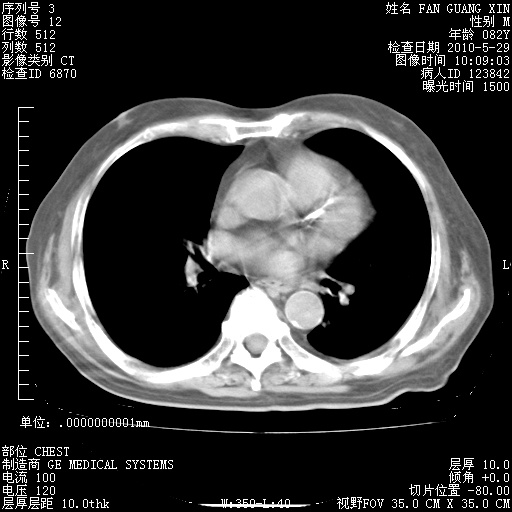

再治疗10天后的肺部CT

再治疗10天后的肺部CT 纵膈窗

阅读此次胸部CT,肺间质渗出性改变较入院时有吸收。目前从体温、白细胞、中性分叶明显增高,肯定存在细菌感染(发生医院感染哦,若无消化道及泌尿系统等感染的依据,肺部感染可能大)。若你院头孢哌酮舒巴坦钠耐药率较高,同意你的方案,若48小时体温仍高,可考虑使用碳青霉稀类抗菌药物,同时可予超声雾化、注意滴数时加大液体量。白蛋白33.30g/L较低哦,需加强营养等支持治疗。